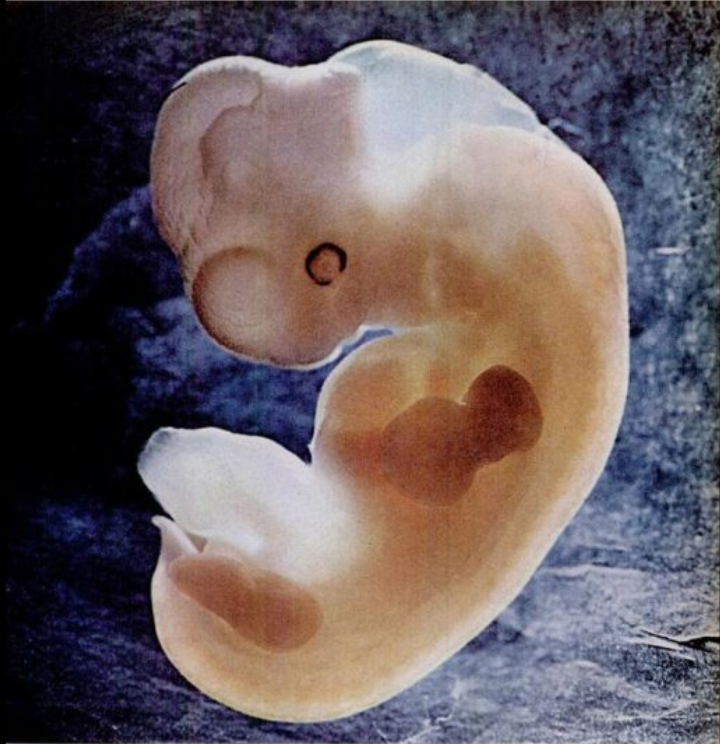

胚胎阶段大约从怀孕第三周持续到怀孕第八周结束。囊胚开始呈现出独特的人类特征。现在它被称为胚胎。神经管(后来成为大脑和脊髓)、头部、眼睛、嘴巴和四肢等结构和器官形成。形成胎儿心脏的细胞在五到六周左右开始聚集并可以搏动。第六周左右也会形成手臂和腿的芽。到第八周结束时,胚胎的大部分器官和系统已经形成。对于很多人来说,这是怀孕期间孕吐开始的时刻。 - 胎儿期

骨骼开始取代软软骨,生殖器开始形成。胚胎的头部与身体其他部分的比例较大。有些人认为胚胎像小蝌蚪或海马,因为它有突出的尾巴(后退)和大头。

所有主要器官和身体系统都在发育。胚胎有网状的手和脚。眼睛变得可见,耳朵开始形成。脐带已完全发育,有助于将氧气和血液输送到胚胎。

第八周后,医疗保健提供者将胚胎称为胎儿。在出生之前它将一直是胎儿。到第二个月末,胎儿的长度约为 0.5 至 1 英寸(英寸),相当于黑豆大小。